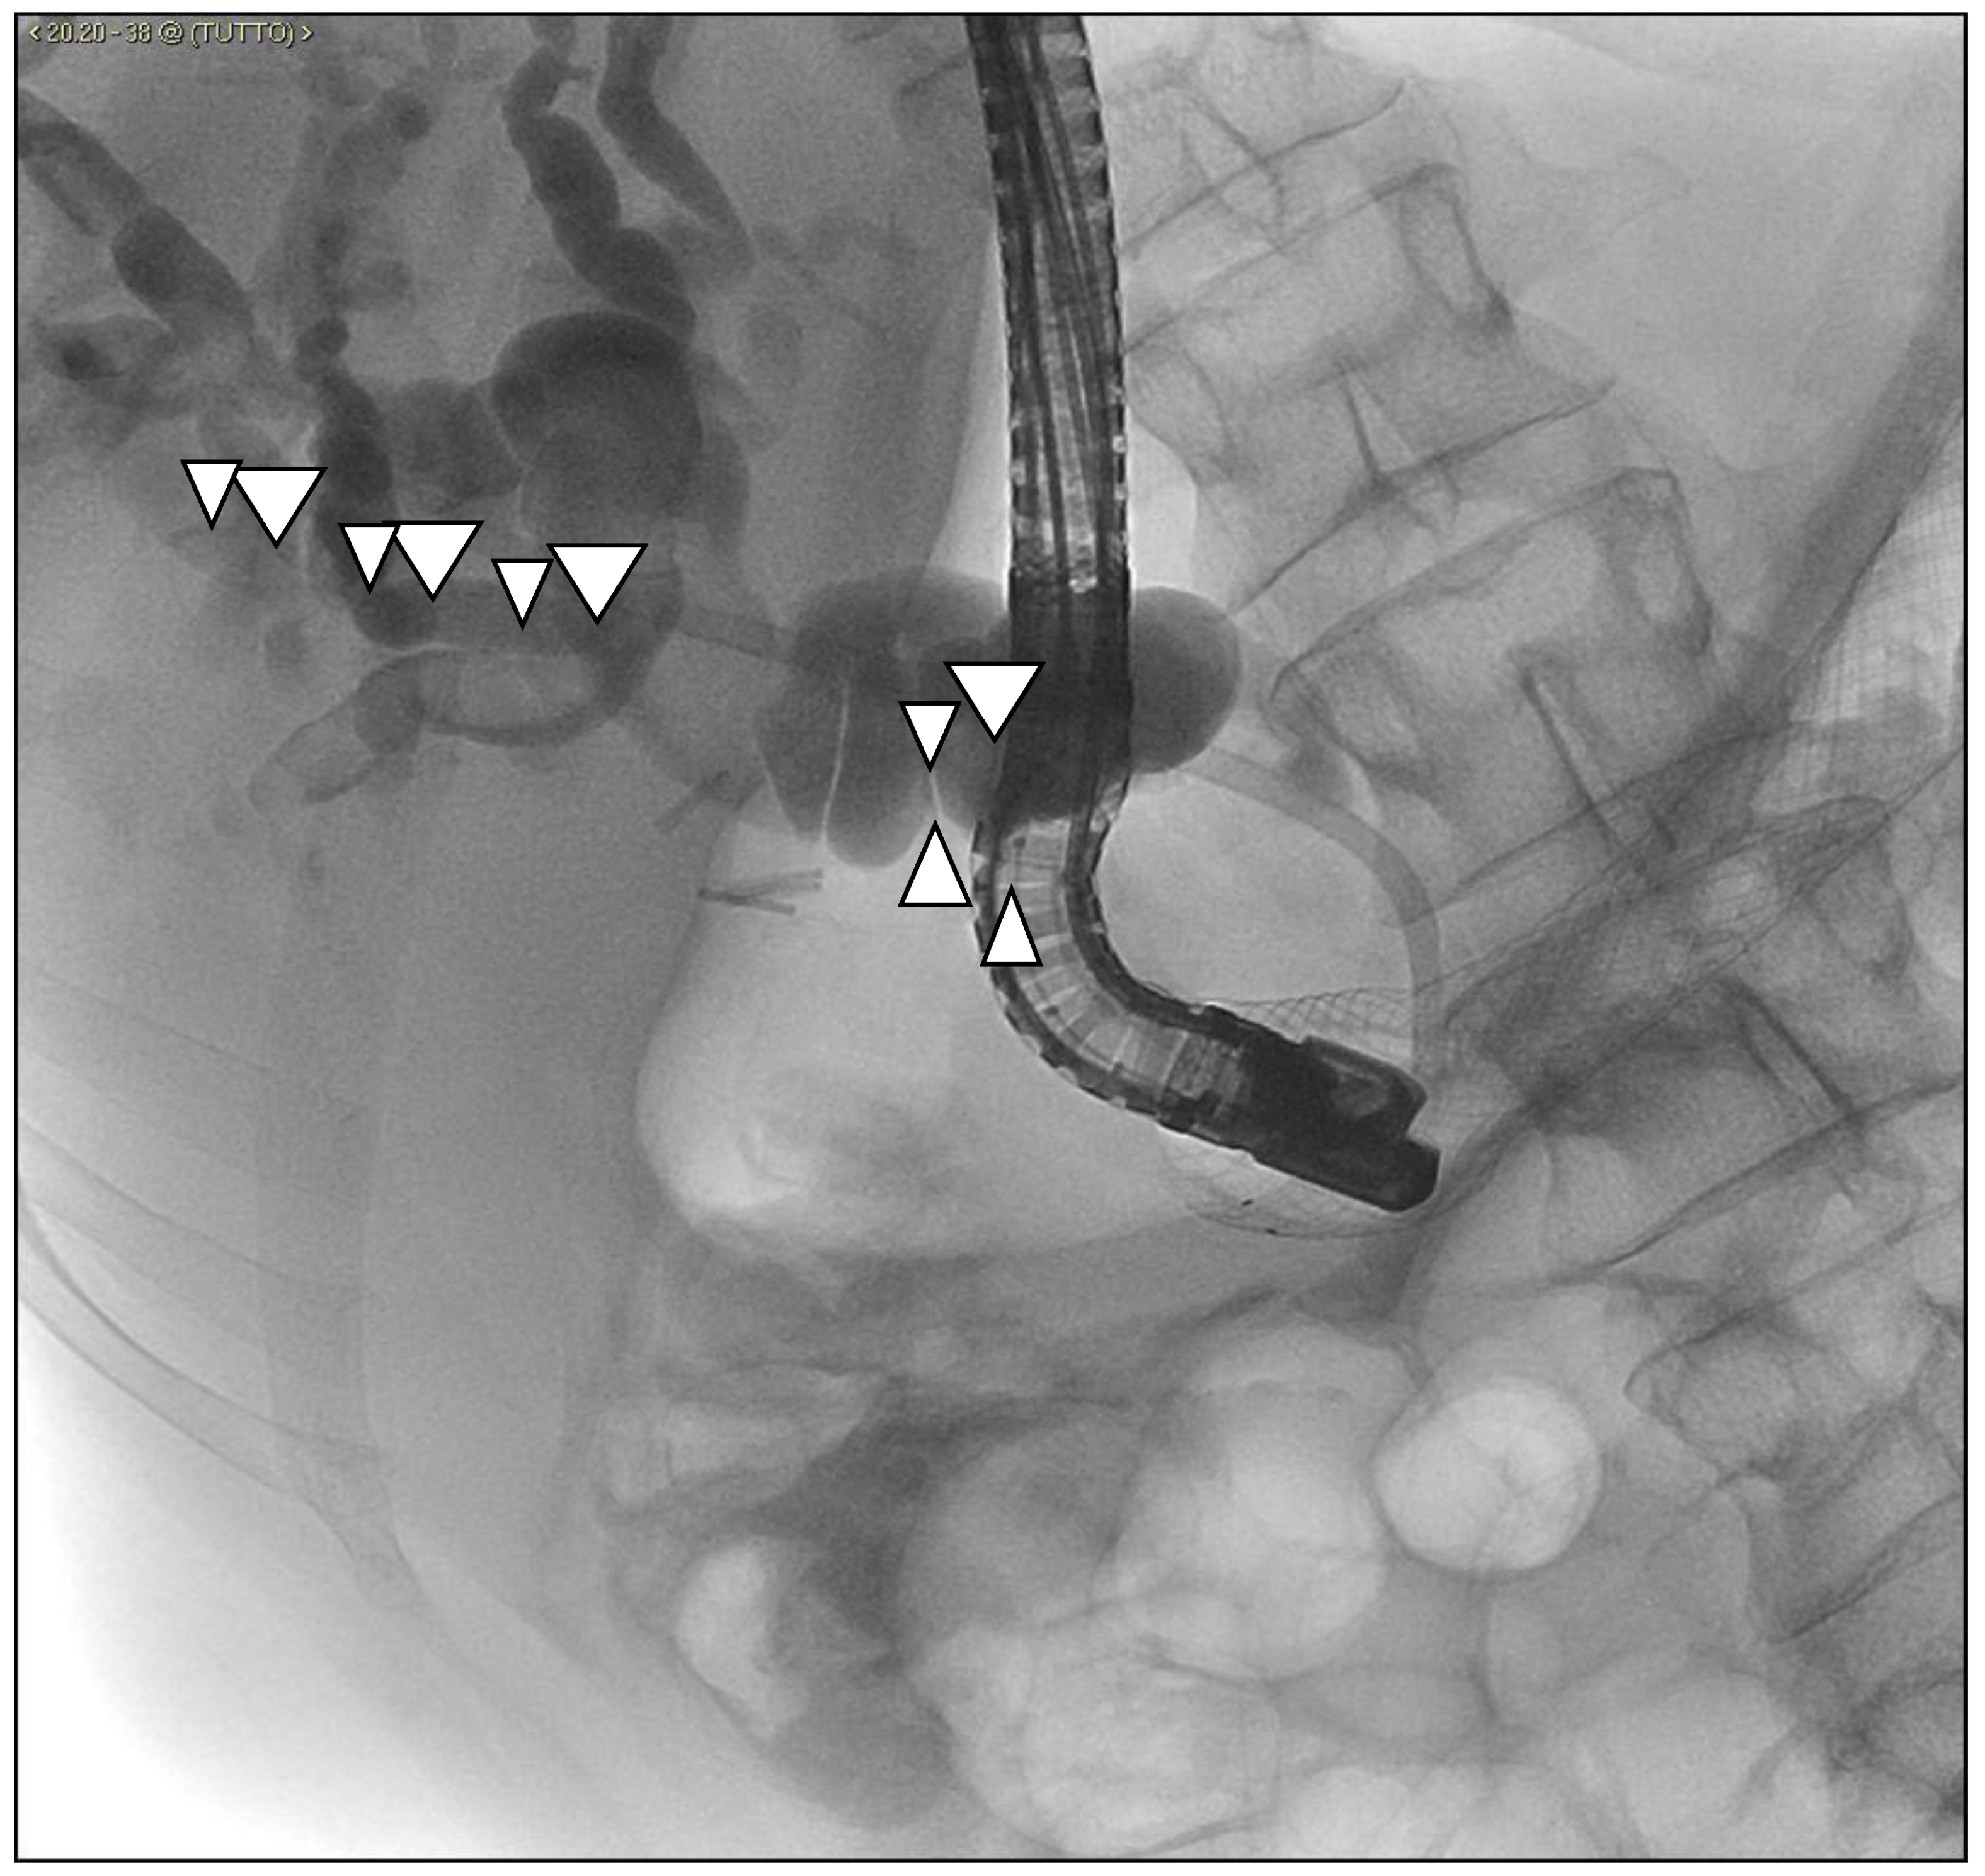

Malignant Gastric Outlet Obstruction Caused by Duodenal Cervix Metastasis in a Young Woman: Rendezvous Technique

2. Case Discussion